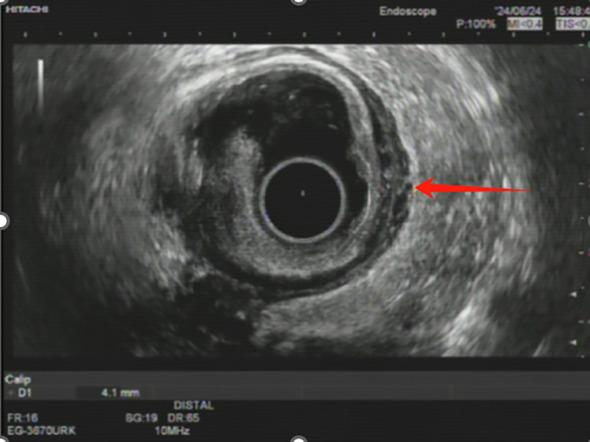

Microsatellite-stable (MSS) rectal adenocarcinoma remains a therapeutic challenge, particularly in patients with complicating factors such as chronic hepatitis B virus (HBV) infection. Advances in immunotherapy, including immune checkpoint inhibitors (ICIs), have introduced new opportunities to improve the treatment outcomes in this subset, yet their application in HBV-positive cancer patients is less well understood. Here we report the case of a 46-year-old female with MSS locally advanced rectal adenocarcinoma and active HBV infection, successfully treated with cmFOLFOXIRI combined with camrelizumab as neoadjuvant therapy. The patient presented with a circumferential rectal mass, elevated tumor markers, and virological evidence of high HBV viral load, necessitating prophylactic antiviral management with entecavir. Following five cycles of cmFOLFOXIRI and two cycles of camrelizumab, significant tumor regression was achieved, with further response observed after long-course radiotherapy combined with irinotecan and capecitabine. Laparoscopic low anterior resection revealed complete pathological remission (pCR), with no residual tumor cells or lymph node metastases identified. This case underscores the potential of integrating immunotherapy into multimodal neoadjuvant regimens for MSS rectal cancer while highlighting the critical importance of HBV management to minimize reactivation risks during treatment. These findings offer valuable insights into the safe and effective use of ICIs in HBV-positive cancer patients, warranting further investigation in larger clinical studies.

微卫星稳定(MSS)的直肠腺癌仍然是一个治疗挑战,尤其是对于伴有慢性乙型肝炎病毒(HBV)感染等复杂因素的患者。免疫疗法的进展,包括免疫检查点抑制剂(ICI),为改善这一亚组患者的治疗结果带来了新机遇,但其在HBV阳性癌症患者中的应用仍了解较少。在此,我们报告一例46岁女性患者,患有MSS局部晚期直肠腺癌且伴有活动性HBV感染,接受了cmFOLFOXIRI联合卡瑞利珠单抗作为新辅助治疗并获得成功。该患者表现为直肠环周肿物、肿瘤标志物升高以及HBV病毒载量高的病毒学证据,因此需要使用恩替卡韦进行预防性抗病毒治疗。经过五个周期的cmFOLFOXIRI和两个周期的卡瑞利珠单抗治疗后,肿瘤显著退缩,在接受长程放疗联合伊立替康和卡培他滨治疗后观察到进一步缓解。腹腔镜下低位前切除术显示完全病理缓解(pCR),未发现残留肿瘤细胞或淋巴结转移。该病例强调了将免疫疗法纳入MSS直肠癌多模式新辅助治疗方案的潜力,同时突出了HBV管理对于将治疗期间再激活风险降至最低的至关重要性。这些发现为在HBV阳性癌症患者中安全有效地使用ICI提供了有价值的见解,值得在更大规模的临床研究中进一步探究。